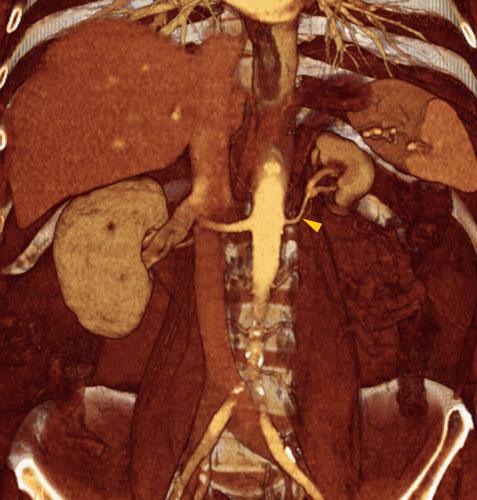

Riñón único pélvico